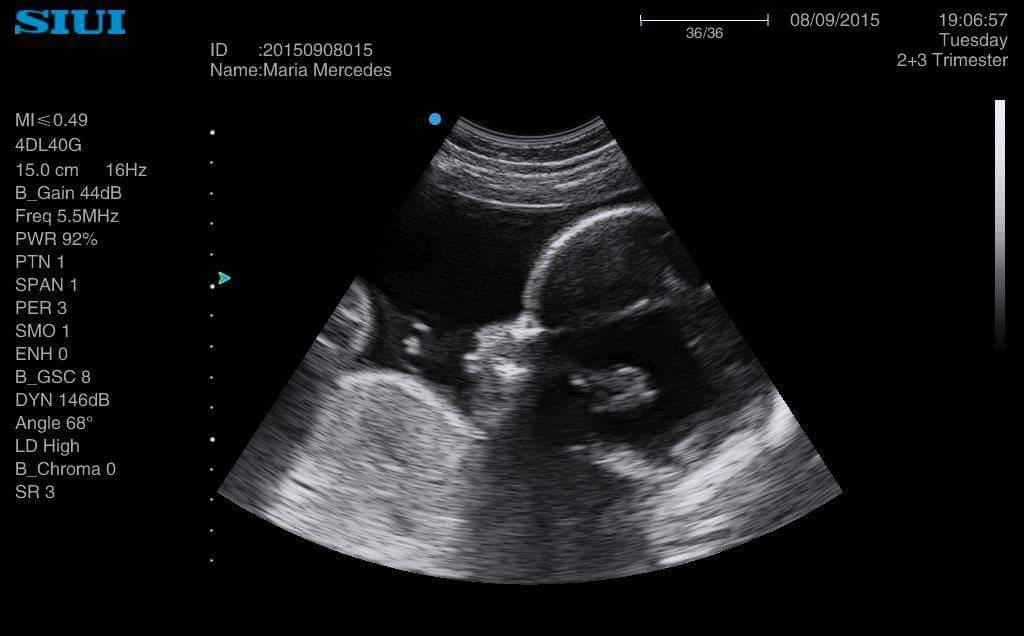

Es la última que nos envía sus ecografías. Solo tiene 18 años. Ha conseguido poder pagarse unas ecografías en 4D. Nos las ha enviado a toda la asociación. Se llama Merce

des y es una de las menores de 20 años que tenemos en los cursos de la asociación. Está tan feliz que se ha puesto a estudiar.

Viene a todo lo que la convocamos. Y ella también nos hace felices a nosotros. La hemos prometido que le pondríamos sus ecografias en este blog para que lo puedan ver todos los rescatadores Juan Pablo II. Como nos comentó hace dos días, parece mentira que hace 5 meses intentara abortar a su hijo. Hoy empieza su tercer trimestre de embarazo. Asociación MásFuturo

Gracias por tu valentía, Mercedes. Eres un gran ejemplo. Nunca te arrepentirás de haber apostado por la vida, por el amor. El camino que has recorrido te ha hecho cambiar. Te ha hecho ver y sentir cosas que nunca pensaste. Elegir lo correcto no suele ser fácil, pero tú has mirado hacia adelante, con entereza y con una sonrisa. Sigue iluminando el mundo con tu sonrisa.